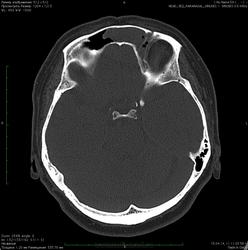

Женщина 58 лет.

Пришла на КТ от ЛОР-врача с диагнозом "хронический фронтальный синусит".

Очень любопытно Ваше мнение -  чем вызвана локальная деструкция задней стенки пазухи?

Субтотальное однородное затенение левой лобной пазухи и " чистые"остальные околоносовые пазухи не исключают объемный процесс от слизистой, в т.ч. с  локальной деструкцией задней стенки, дифференцировать с мукоцеле.

мукоцеле + "атрофия от давления"- может быть, но и гнойный фронтит с деструкцией задней стенки  нельзя не учитывать.

По нативной КТ - в головном мозге все спокойно.

кстати деструкция здесь не только задней стенки, но и нижней - кистозное образование (а их тут я насчитал 2) распространяется в решетчатую кость, занимая часть ее ячеек.